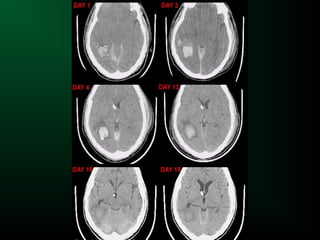

Hématome intracérébral

Hématome intracérébral et Scanner

Stade subaigu :

– 1 à 6 semaines

– Evolution de la périphérie vers le centre

– L’hyperdensité devient progressivement isodense